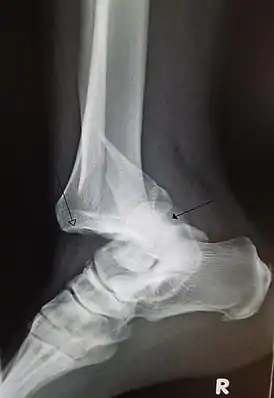

![]() Перелом нижней трети правой малоберцовой кости со смещением и вывихом стопы кзади | |